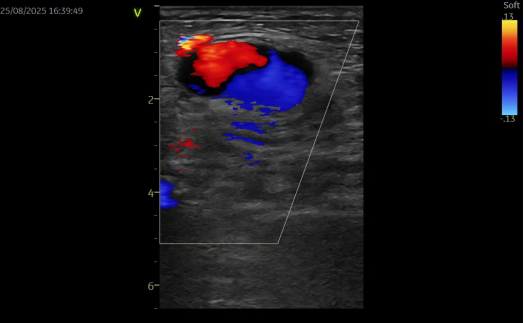

床旁超声检查提示:腹股沟区皮下可见特定范围的无回声区,边界清楚、形态欠规则,可见通道与动脉相连,动脉持续血流灌注;CDFI 示动脉与包块间分流口内可探及双向血流,包块内血流紊乱呈涡流,结合临床症状及检查结果,考虑为假性动脉瘤。

超声引导下凝血酶封堵术已成为临床处理假性动脉瘤的常用微创方式之一。该患者的手术过程顺利,在注射凝血酶 1 分钟后,超声复查显示瘤腔内活动血流消失,瘤体已血栓化,动脉与假性动脉瘤的通道封闭,听诊杂音及体表震颤感均消失。术后患者不适症状得到缓解,恢复顺利,次日出院(此为该患者个体恢复情况,不同患者因病情严重程度、体质、合并基础疾病等差异,恢复周期及效果可能不同)。